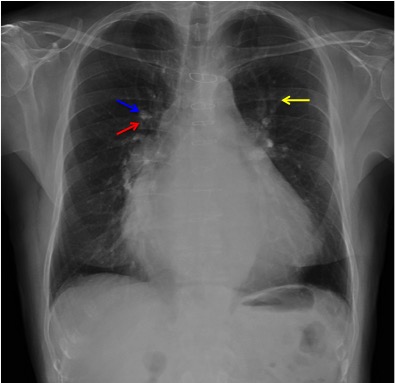

CASO: Disnea. Paciente con insuficiencia cardiaca.

Hallazgos:

- Cardiomegalia.

- Signo del 3º mogul y doble contorno por crecimiento de la aurícula izquierda.

- Bronquio izquierdo rectificado por crecimiento de la aurícula izquierda (signo de la bailarina).

- En la placa lateral, además se observa elongación aórtica.

- Parénquimas pulmonares sin hallazgos.

Signo del doble contorno: La AI aumentada de tamaño produce un segundo contorno que normalmente no debería figurar (flecha naranja contínua).

Flecha amarilla: cayado aórtico.

Flecha verde: arteria pulmonar.

Flecha azul: ventrículo izquierdo.

Signo del tercer mogul: se refiere a la lobulación anormal del contorno mediastínico izquierdo entre la arteria pulmonar y el ventrículo izquierdo. Pueden producir esta lobulación lesiones cardíacas y pericárdicas (orejuela izquierda aumentada, aneurisma ventricular o de la arteria coronaria, quiste o masa pericárdicos, etc) y también algunos tumores mediastínicos, como timomas. En la imagen, el signo corresponde al crecimiento de la orejuela izquierda (flecha roja). La palabra “mogul” es un término utilizado por los esquiadores para describir un acúmulo mamilar de nieve compacta en una ladera montañosa. El primer mogul corresponde al cayado aórtico (flecha amarilla); el segundo, a la prominencia de la arteria pulmonar (flecha verde); y el cuarto, al contorno del ventrículo izquierdo (flecha azul).

Signo del doble contorno: indicativo de crecimiento de la aurícula izquierda en la radiografía posteroanterior de tórax. La aurícula izquierda no forma parte normalmente del contorno cardiaco derecho en esta proyección; sin embargo, cuando aumenta de tamaño, produce un segundo contorno (flecha narana contínua), además del de la aurícula derecha (flecha naranja discontinua).

Signo de la bailarina: es un signo de crecimiento de la aurícula izquierda visible en la radiografía posteroanterior o anteroposterior de tórax, y consiste en el aumento del ángulo traqueal por levantamiento del bronquio principal izquierdo (flecha rosa). El nombre del signo se debe al parecido de la imagen con la apertura de piernas (spagat) de una bailarina.